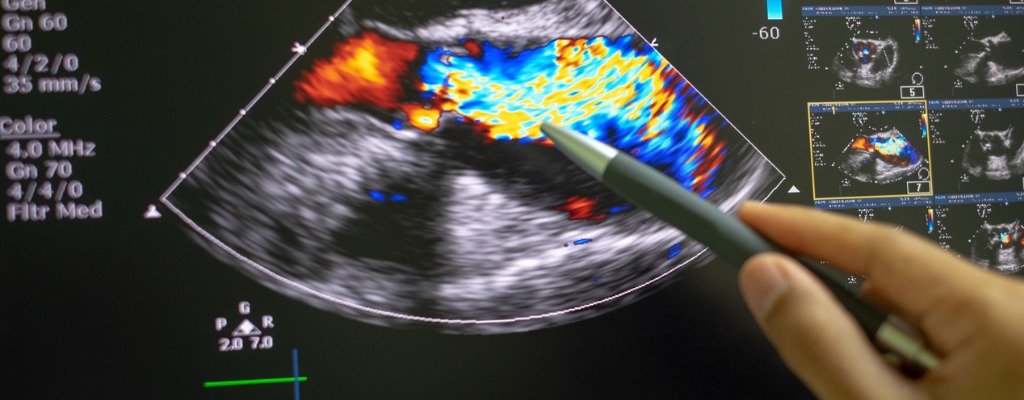

NDI radiologists use teleradiology services and a PACS technology to transmit radiological patient images, such as x-rays, CTs, ultrasounds, mammograms, echocardiograms and MRIs, from one location to another in order to share radiology imaging studies and reports with other radiologists, referring physicians and patients.

The NDI telecardiology company provides remote online reporting of cardiac imaging studies of the circulatory system, cardiovascular system, heart and blood vessels. NDI telecardiology services are used by U.S. cardiovascular imaging centers to receive remote interpretations of electrocardiogram (ECG or EKG) results from heart imaging specialists online.